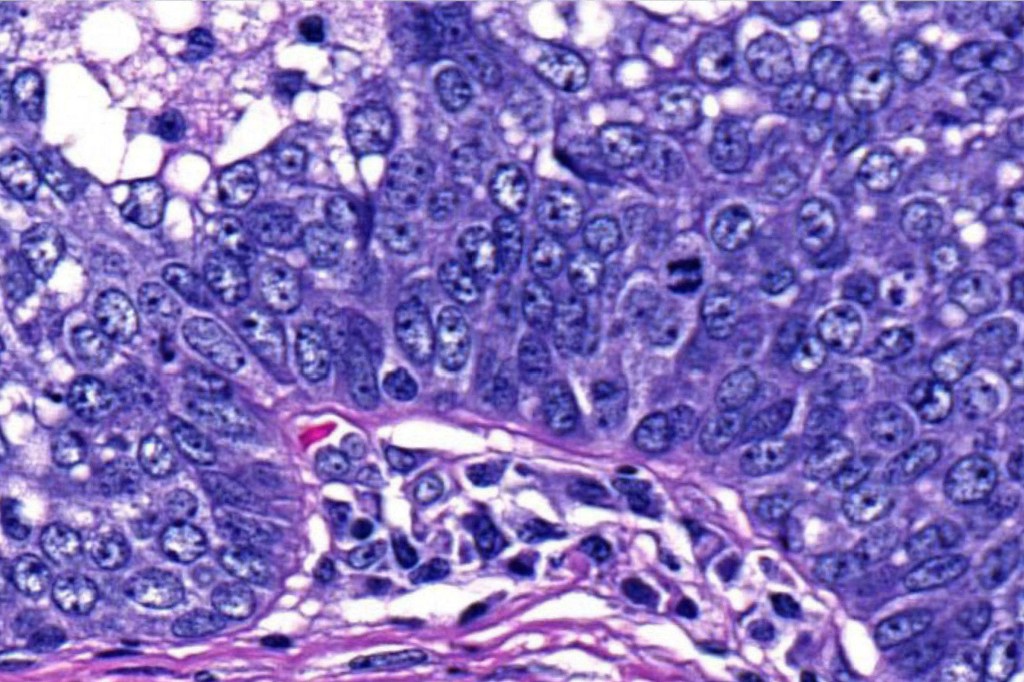

•Tumors are composed of an admixture of darkly staining basaloid cells with hyperchromatic or vesicular nuclei and more obvious sebaceous cells with eosinophilic, bubbly, multivacuolated cytoplasm frequently indenting the nucleus (scalloped)

•Often mitoses are numerous and abnormal forms evident

•Variable Lymphovascular invasion & perineural infiltration

Sebaceous carcinoma from a patient with Muir-Torre syndrome kindly shared by Dr. Antonina Kalmykova.